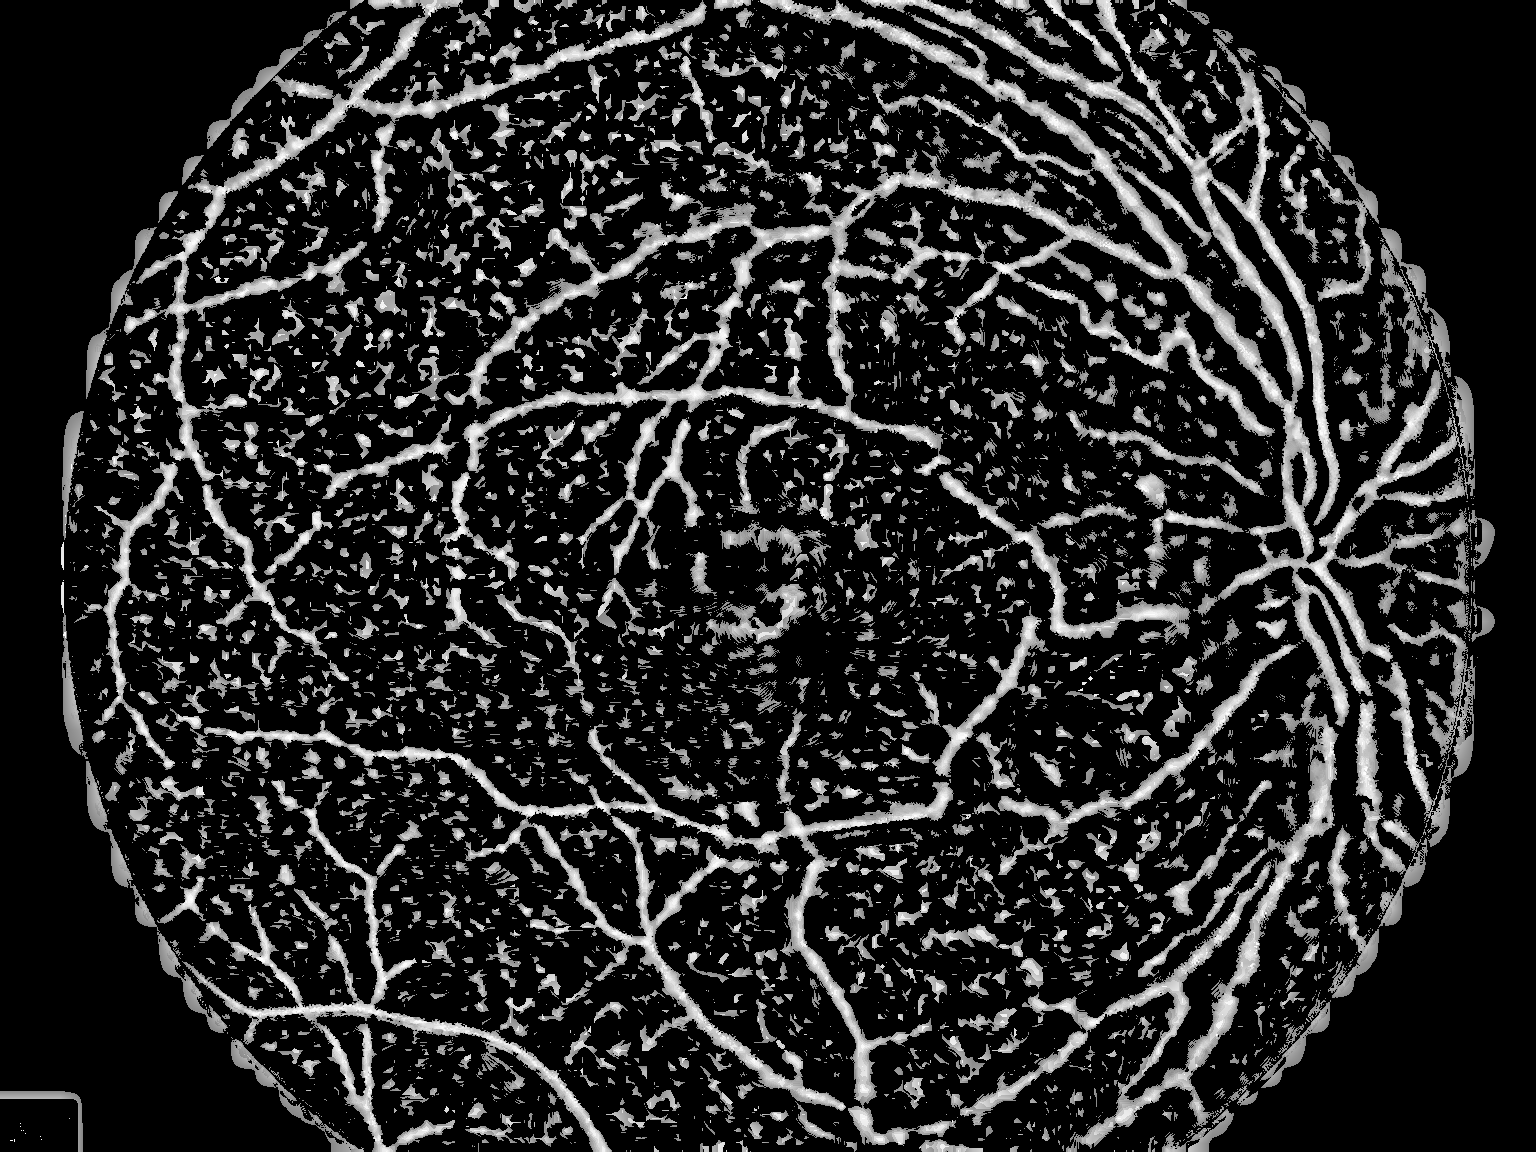

结果

这绝不是最优的,但我认为它应该为您提供足够的启动工具。

如何:高通(图像减去高斯平滑与西格玛12),然后阈值(126),然后小目标抑制(小于300个像素的对象被删除)?

(我用了你的上一张照片)